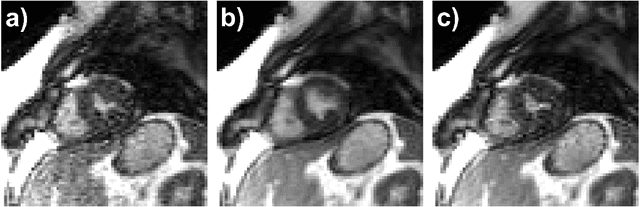

Abstract:Real-time (RT) dynamic MRI plays a vital role in capturing rapid physiological processes, offering unique insights into organ motion and function. Among these applications, RT cine MRI is particularly important for functional assessment of the heart with high temporal resolution. RT imaging enables free-breathing, ungated imaging of cardiac motion, making it a crucial alternative for patients who cannot tolerate conventional breath-hold, ECG-gated acquisitions. However, achieving high acceleration rates in RT cine MRI is challenging due to aliasing artifacts from extra-cardiac tissues, particularly at high undersampling factors. In this study, we propose a novel outer volume removal (OVR) method to address this challenge by eliminating aliasing contributions from non-cardiac regions in a post-processing framework. Our approach estimates the outer volume signal for each timeframe using composite temporal images from time-interleaved undersampling patterns, which inherently contain pseudo-periodic ghosting artifacts. A deep learning (DL) model is trained to identify and remove these artifacts, producing a clean outer volume estimate that is subsequently subtracted from the corresponding k-space data. The final reconstruction is performed with a physics-driven DL (PD-DL) method trained using an OVR-specific loss function to restore high spatio-temporal resolution images. Experimental results show that the proposed method at high accelerations achieves image quality that is visually comparable to clinical baseline images, while outperforming conventional reconstruction techniques, both qualitatively and quantitatively. The proposed approach provides a practical and effective solution for artifact reduction in RT cine MRI without requiring acquisition modifications, offering a pathway to higher acceleration rates while preserving diagnostic quality.